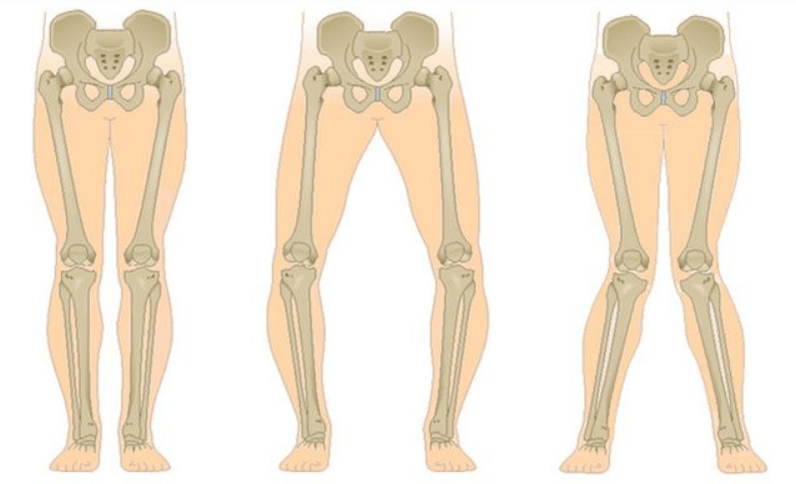

The last stage of gonarthrosis is distinguished by the fact that the pain becomes almost constant, causing anxiety not only when walking, but also when resting and even at night, when the patient needs to find a comfortable position to sleep.Movement is more limited: it is difficult to fully bend and straighten the leg.The joint becomes deformed and increases in volume.Valgus (X-shaped) or varus (O-shaped) deformity of the legs is often observed.The gait becomes unstable and staggers.In severe cases, a cane or crutches are required.

In arthrosis (osteoarthrosis), in addition to the progressive destruction of cartilage, loss of elasticity and shock-absorbing properties, bones are gradually involved in the process.Under load, sharp edges (exostoses) appear, which are mistakenly considered “salt deposits” - in classic arthrosis, salt deposition does not occur.As osteoarthritis progresses, it continues to “eat” the cartilage.Then the bone becomes deformed, cysts form, all joint structures are affected and the leg becomes bent.